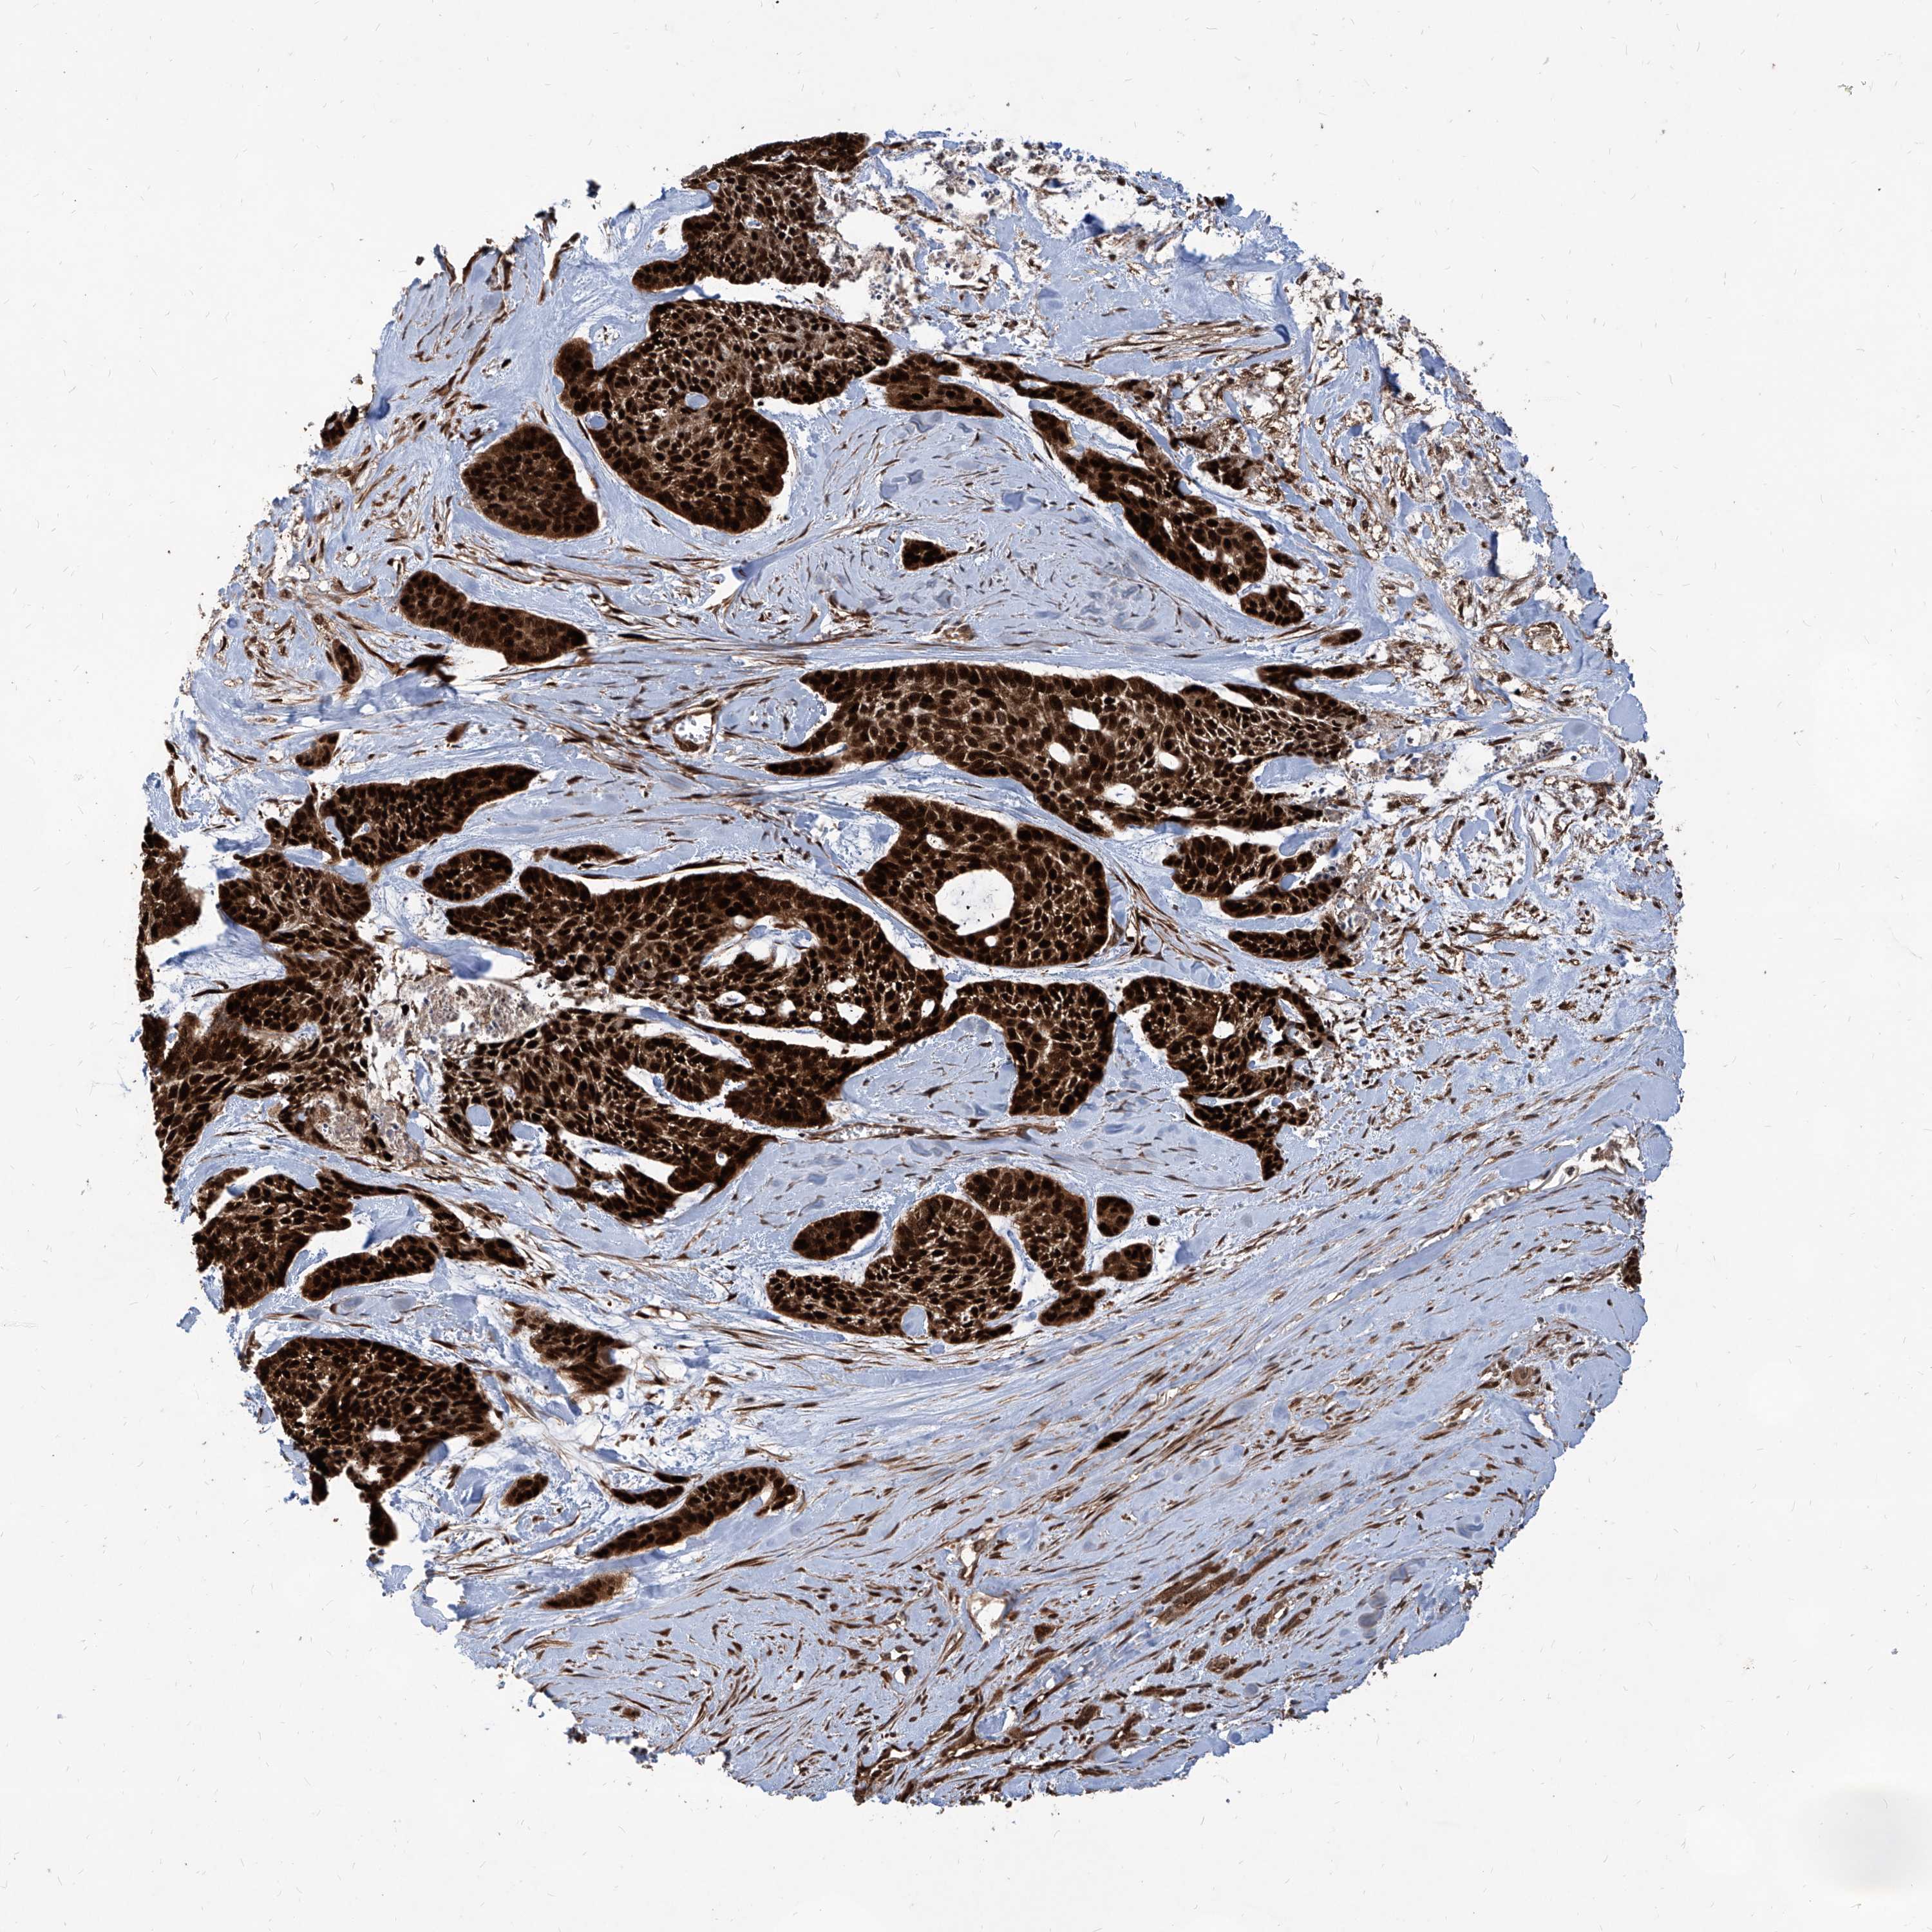

SKIN CANCER - Protein expressioni

A mouse-over function shows sample information and annotation data. Click on an image to view it in a full screen mode. Samples can be filtered based on level of antibody staining by selecting one or several of the following categories: high, medium, low and not detected. The assay and annotation is described here.

Antibody staining in the annotated cell types in the current human tissue is reported as not detected, low, medium, or high, based on conventional immunohistochemistry profiling in selected tissues. This score is based on the combination of the staining intensity and fraction of stained cells.

Each image is clickable and will lead to virtual microscopy that enables deeper exploration of all samples and also displays staining intensity scores, fraction scores and subcellular localization as well as patient and tissue information for each sample.

Antibody HPA031572

Antibody HPA031573

Squamous cell carcinoma, NOS

Squamous cell carcinoma, metastatic, NOS